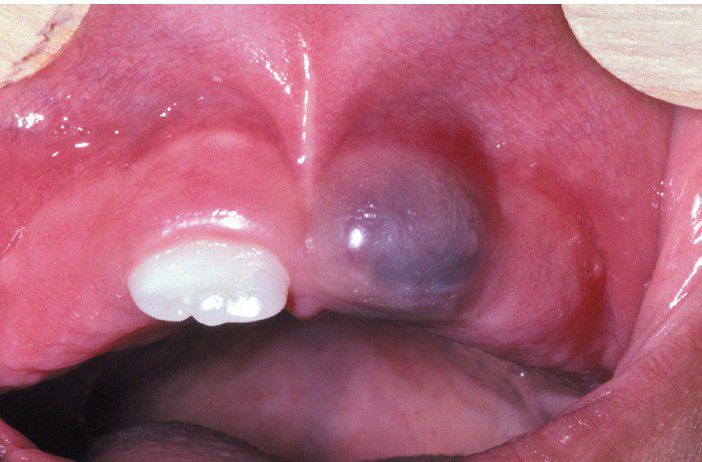

Eruption Cyst

. This soft gingival swelling contains considerable blood and can also be designated as an eruption hematoma.